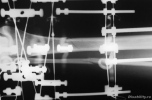

Что ж, товарищи, чуда не произошло, еще минимум два месяца я буду с вами. Сделали снимок. Костная мозоль видна, врач говорит, хорошая. Но до полного сращения еще дело не доходит даже близко. Так что велели прийти после ноябрьских праздников.

Аппарат ИлизароваНу вот, сделала снимки, начну выкладывать. Вот что было через 15 дней после наложения аппарата. Снимок номер раз.